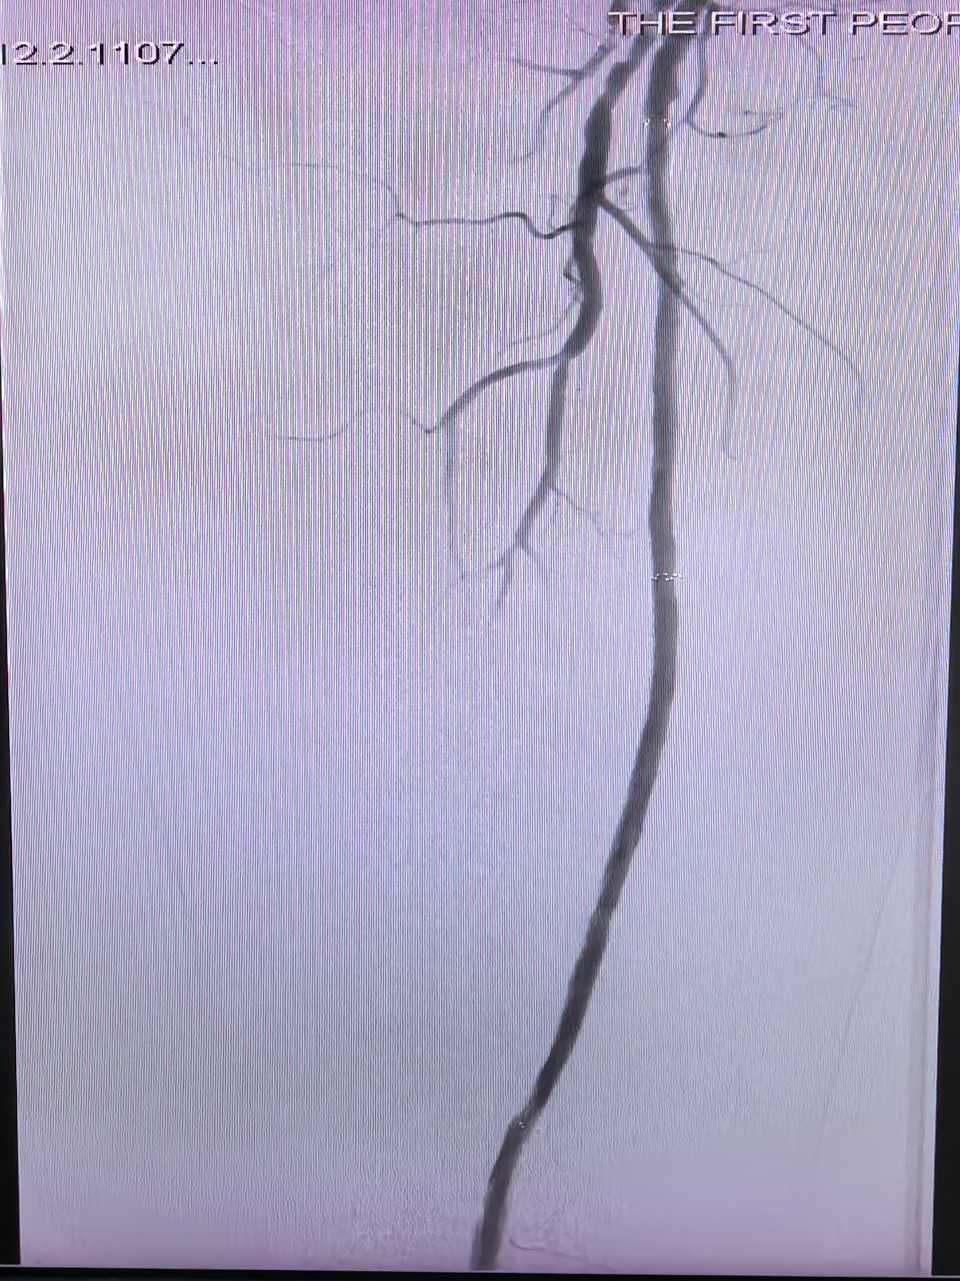

3.术后复查造影:股浅动脉血管支架内血管恢复通畅

经过精心准备手术如期开展。介入与血管外科团队在DSA血管造影机引导下,严格按照操作流程,高速旋切及清除血管、支架各处的斑块等阻塞物,经过1小时操作,斑块清除彻底,闭塞血管成功开通,恢复血流。术后,患者足趾颜色马上从紫绀变回红润,皮肤温度也恢复正常,手术取得圆满成功。